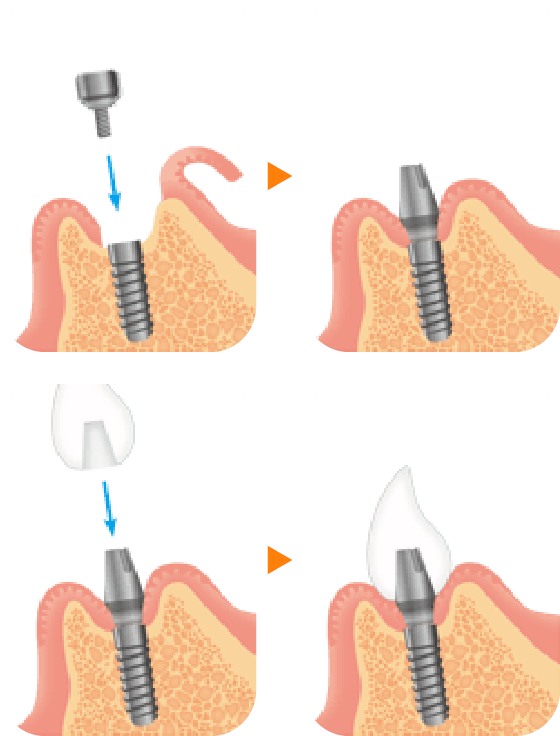

インプラント治療は人工歯根治療ともいわれ、虫歯や歯周病、歯の破折などで失った歯のかわりに人工歯根(インプラント)をアゴの骨に埋め込み、その上に支台部(アバットメント)と人工歯を装着する治療法です。

3 一次手術

(インプラント埋入)

アゴの骨にインプラント(人工歯根)を埋め込む手術を行います。局所麻酔を使用し、歯肉を切開して歯槽骨を露出させ、ドリルを使って孔を開け、インプラントを埋め込みます。最後に歯肉を縫い合わせます。経験豊富な歯科医師が担当しますので、インプラント1本あたり15分から20分程で手術は終わります。(骨移植など、骨造成を併用する場合はさらに時間を要します。)術後、2~3日程歯肉や頬が腫れる場合や、内出血がみられる場合があります。抗生剤と痛み止めを服用していただきます。

5 二次手術

(1回法では必要ありません。)

歯肉を開き、頭出しを行い、人工の歯を装着する準備をします。この状態で歯肉が治癒し安定するのを待ちます(1~4週間)。

6 型取りと人工の

歯の装着・完了

歯肉が治癒したら、型を取り、支台部(アバットメント)と人工の歯を作製し装着していきます。多くの場合、支台部はスクリューで固定し、人工の歯はセメントで固定し治療完了です。当院では人工の歯はもちろんのこと、支台部も患者様それぞれにあったカスタムメイドになりますので型取りから装着まで作製期間として2週間かかります。